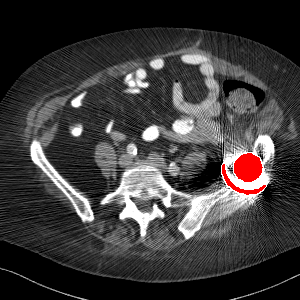

Visual comparison. As shown in Fig. 5, metallic implants such as spinal rods and hip prosthesis cause severe streaky artifacts and metal shadows, which obscure bone structures around them. cGan-CT cannot recover image intensity correctly for both cases. Sinogram domain or dual-domain methods perform much better than cGan-CT. LI, NMAR, and CNNMAR introduce strong secondary artifacts and distort the whole images. In NMAR images, there are fake bone structures around the metals, which is related to segmentation error in the prior image from strong metal artifacts. The segmentation error is also visible in NMAR sinogram. CNNMAR cannot restore the correct bone structures between rods in case 1. The tissues around the metals are over-smoothed in DuDoNet because LI sinogram and image are used as inputs, and the missing information cannot be inferred later. Our model retains more structural information than DuDoNet and generates anatomically more faithful artifact-reduced images.

Visual comparison. Fig. 7 shows two clinical CT images with metal artifacts. Case 1 is with moderate metal artifacts. cGan-CT does not suppress the artifacts completely and generates some fake details. LI, NMAR, CNN-MAR remove all the artifacts but introduce new streak artifacts, which is caused by the discontinuity in the corrected sinogram. DuDoNet outputs over-smoothed sinogram, which leads to blurred tissues close to the metal implants, such as muscle and bone. Only our model can provide realistic enhanced sinogram and remove the artifacts while retaining the structure of nearby tissues. Case 2 is very challenging as the rods bring strong metal shadows and bright artifacts around the vertebra. cGan-CT recovers the shape of vertebra but changes the overall image intensity. Other sinogram inpainting methods fail as the soft tissue and bone near the rods are heavily distorted. Our model removes part of the dark bands and reproduces correct anatomical structures around the rods.